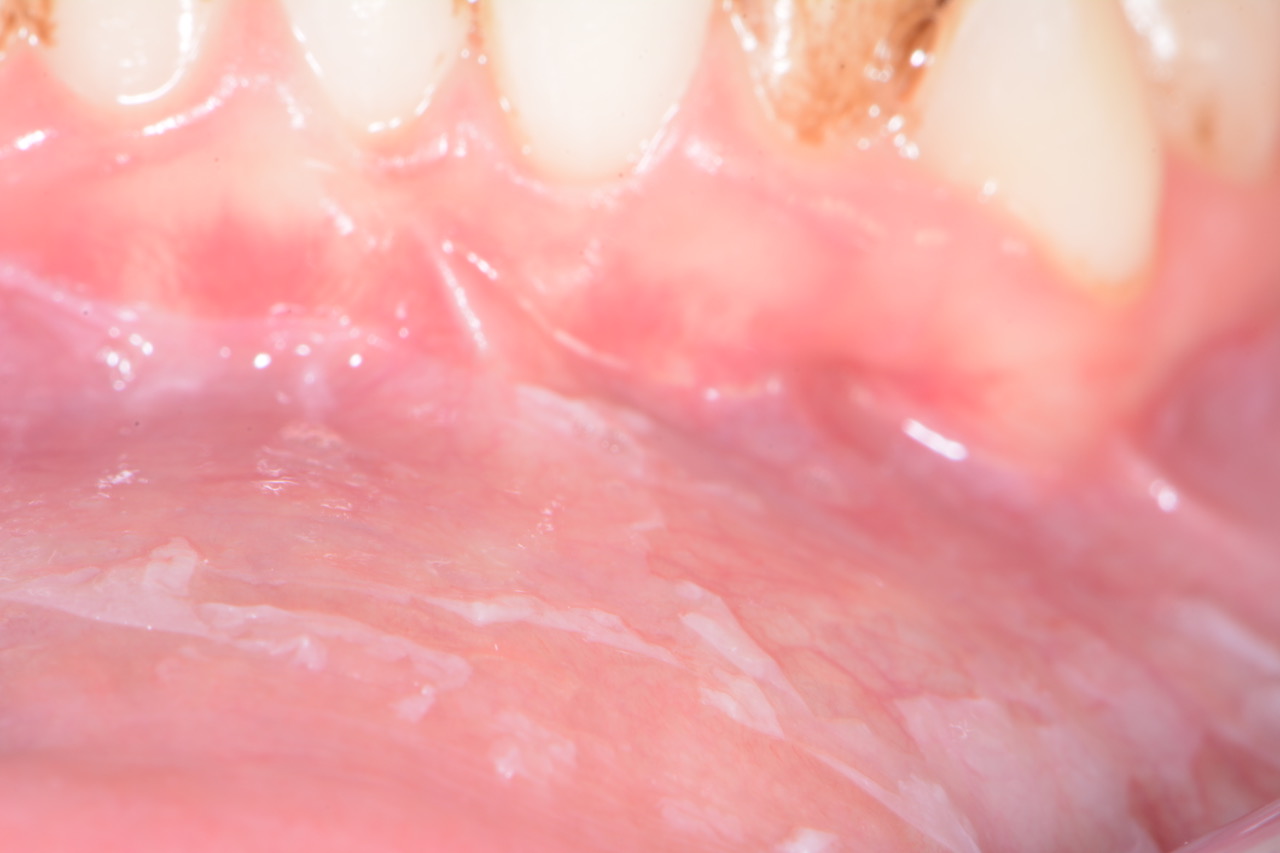

Si è infatti notato come esso tenda, in alcuni soggetti/pazienti, a provocare un distaccamento, un peeling delle mucose orali che appaiono sfilacciate, a strisce e che possono essere rimosse facilmente dallo spazzolamento.

In questi casi appare quindi importante intervenire repentinamente, eliminando dalla cavità orale qualsiasi stimolo chimico (inclusi tutti i dentifrici) e controllare successivamente se vi sia o meno un miglioramento della sintomatologia clinica. Nel caso questo non si avverasse, va consultato quanto prima un patologo orale.